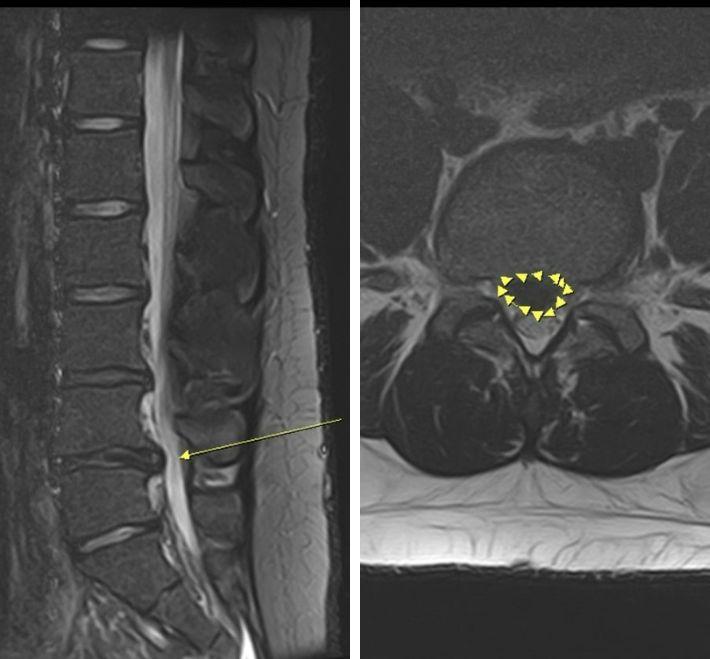

【椎間盤突出最新指南】從成因症狀到非手術與微創治療全解析

椎間盤突出一定要開刀嗎?張建鈞醫師團隊根據 2026 最新醫學文獻,深度解析椎間盤突出成因與紅旗警訊。研究證實約 70% 突出有機會自行吸收!本文涵蓋非手術復健,到 3D 導航內視鏡手術的精準醫療趨勢,助您精確判斷最佳治療時機,擺脫坐骨神經痛,找回脊椎健康。